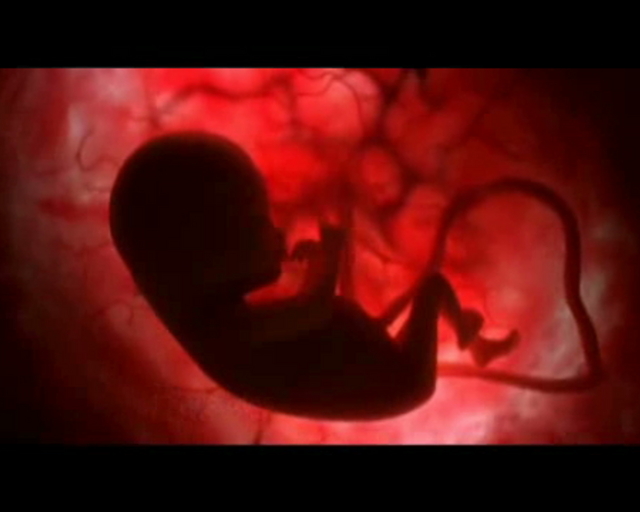

Ο ρόλος των υδατανθράκων για την ομαλή ανάπτυξη του εμβρύου

Μια διατροφή με χαμηλή περιεκτικότητα σε υδατάνθρακες κατά την κύηση ίσως αυξάνει τον κίνδυνο απόκτησης παιδιού με σοβαρές γενετικές ανωμαλίες, σύμφωνα με αμερικανική μελέτη που δημοσιεύεται στο επιστημονικό έντυπο Birth Defects Research.